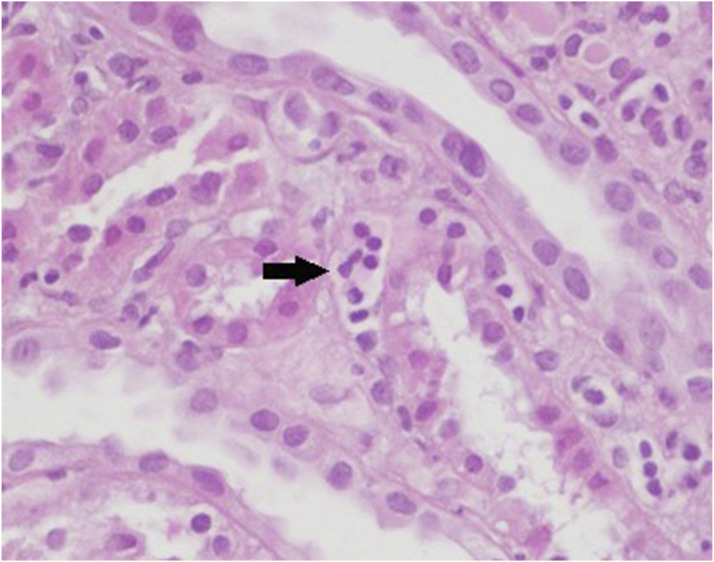

背景与目的系统性红斑狼疮患者出现狼疮性肾炎与较短的死亡时间相关。本研究的目的是确定小管周围毛细血管炎(ptc)的频率及其与狼疮性肾炎活动性和慢性病变的关系。材料-方法对57例患者的标本进行重新评价。根据Banff分类评估每次活检中小管周围毛细血管的炎症程度,并进行ptc评分。此外,根据高/低活动和慢性指数评分对患者进行分组。结果女性45例(78.9%),平均年龄27.43岁。Ptc患者45例(78.9%),Ptc评分为1、2、3分的患者分别为20例(35.08%)、20例(35.08%)、5例(8.7%)。与正常肌酐水平的患者相比,血清肌酐升高(>1.20 mg/dL)的患者更常检测到严重的ptc(评分2或3)(92.3% vs 29.5%, p < 0.001)。4类患者的ptc严重程度高于3类患者(68.2% vs 21.7%, p = 0.005)。活动指数为6或以上的患者ptc得分高的比例高于活动指数为6以下的患者(62.5% vs 30.3%, p = 0.032)。慢性指数与ptc无显著相关性。结论ptc是狼疮性肾炎患者常见的病理特征。此外,ptc的严重程度似乎与血清肌酐水平升高呈正相关,较高的ptc评分更常见于活动指数高的病例。